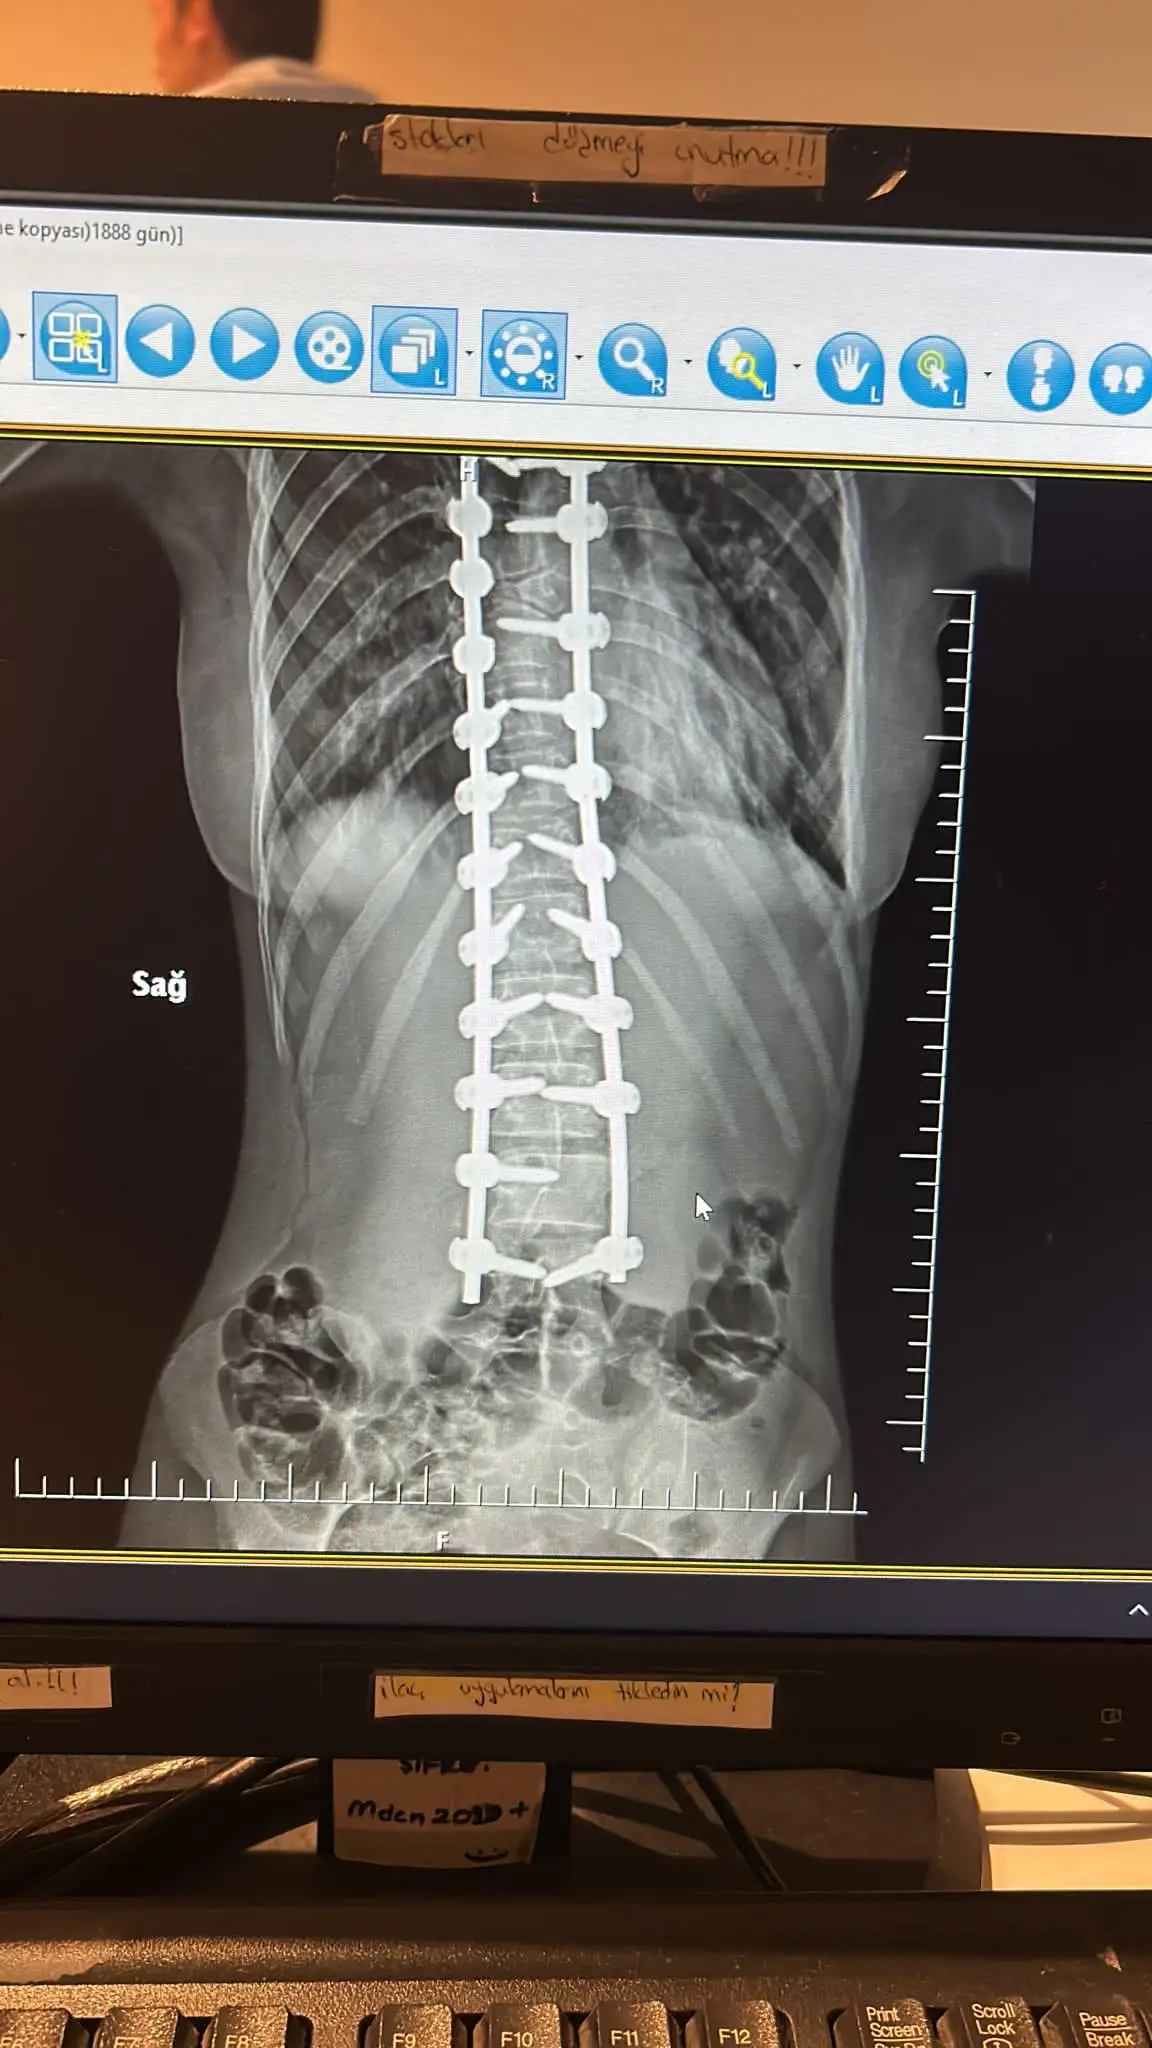

Hello, people with big hearts! Our lovely Aissy went through a second very difficult and complicated spinal surgery. Due to the abnormalities she has , more implants were placed than intended. She is in a serious condition and the scary panic attacks have started. He can't get out of bed and refuses to eat. Despite everything we with the help of the doctors , are fighting her condition to improve. For this purpose, however, the funds left in the account , are very insufficient. I ask you from my heart and soul, Help us , Icy to chase and fulfill her dreams! Share our campaign to reach as many people as possible to answer our cry for help! This beautiful child, has to live! Thank you! Take a bow!